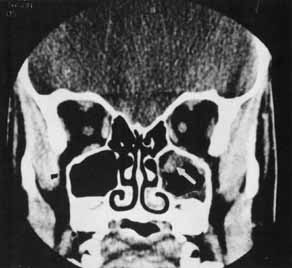

Fracture of the lamina papyracea may occur in association with orbital floor fractures. Isolated medial wall fractures rarely result in complications. Significant enophthalmos may occur in large medial wall fractures, depending on the amount of tissue prolapsed into the sinuses.50 The medial rectus muscle may become incarcerated in the fracture site, resulting in pain and limitation with attempted abduction (Fig. 11).50–52

Fig. 11 CT scan demonstrates the left medial rectus displaced medially into the fracture site (arrow).